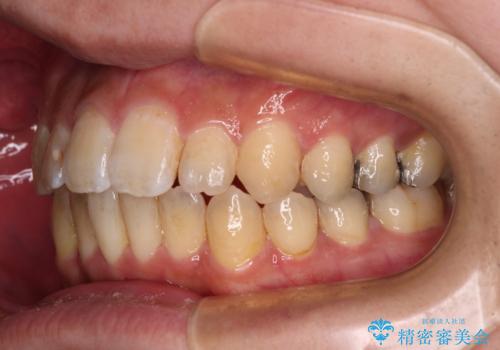

オープンバイトと目立つ銀歯 インビザライン矯正とセラミック修復治療

- 奥歯の目立つ銀歯と上下前歯の叢生と隙間を気にして来院された患者様です。

開咬の治療は、前歯を閉じるように動かすとともに、上下臼歯を圧下(骨内にめり込ませる)させることで進めて行きます。

インビザラインは臼歯の圧下を効果的に行えるため、インビザラインを用いて矯正治療を行うこととしました。